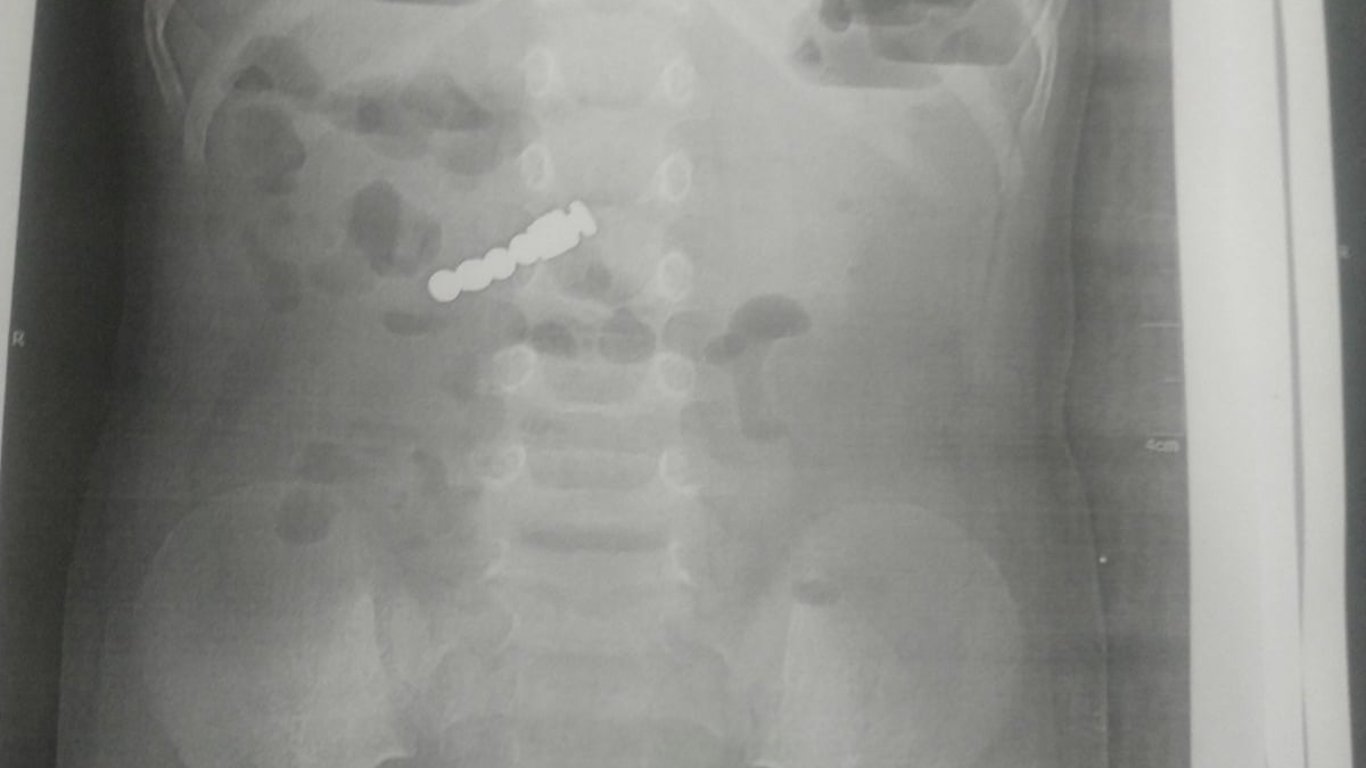

На Львовщине 2-летняя девочка проглотила магниты, приняв их за конфеты. Ребенок ходил с металлом в животе не менее десяти дней.

Во Львовской области двухлетняя девочка проглотила четыре магнита - она гостила у бабушки и взяла игрушки старших внуков.

"Маленьких жертв магнитов не становится меньше, именно по этой причине мы напоминаем взрослым о магнитной опасности для малышей. Когда магнитики попадают в детские желудки, то могут наделать немало беды. Магниты имеют необычайную силу притяжения, поэтому повреждают внутренние органы ребенка, случается, иногда они пробивают их и образуют настоящие дыры. Уже через несколько часов магнитики могут стать причиной некроза кишки", – сообщили в больнице.

Когда девочку привезли в больницу, у нее были только тошнота и повышенная температура. Ей сделали рентген, и тогда оказалось, что у девочки внутри находятся аж четыре магнита. Ребенок проглотил их десятью днями раньше, когда гостил у бабушки. Магниты удалось удалить, и сейчас с девочкой все в порядке.

"Доставали их наши хирурги с помощью современного электронно-оптического преобразователя (ЭОП) в ургентной операционной, что обеспечило точные и успешные манипуляции разного уровня сложности. Малышня получила медикаментозное лечение и на 3 день ее выписали домой", – рассказали врачи.